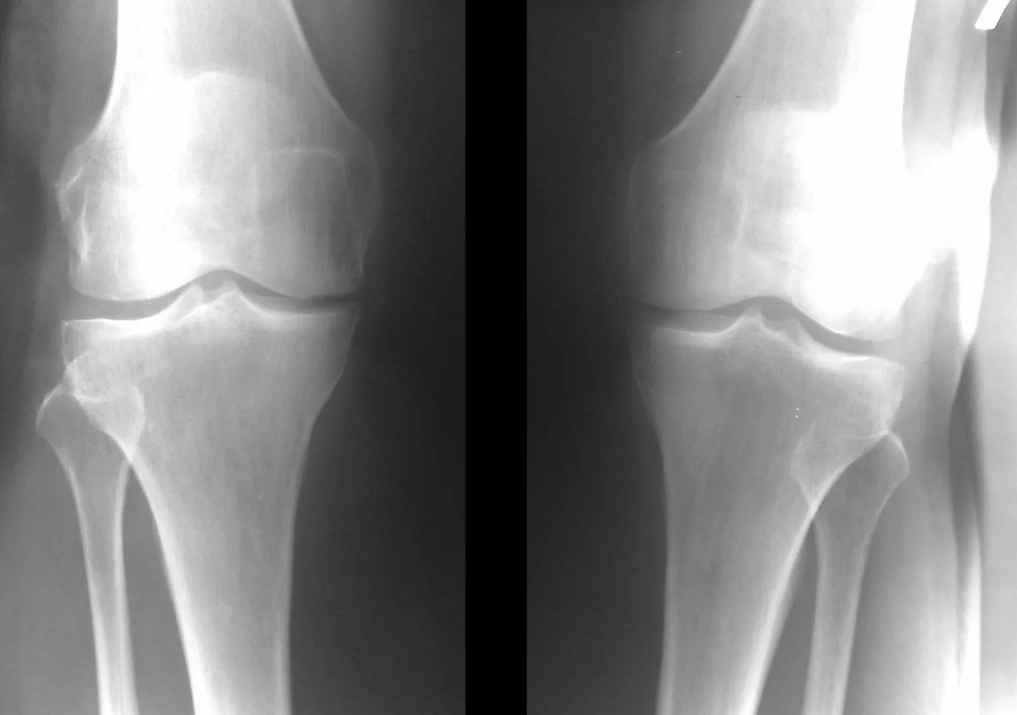

Nella stragrande maggioranza dei casi sono sufficienti un esame e una radiografia dell'articolazione del ginocchio in due proiezioni (diretta e laterale). I dati clinici e le immagini aiutano a determinare lo stadio della malattia.

Nelle fasi iniziali della malattia, con lievi cambiamenti nel tessuto osseo, l'esame radiografico non è così prezioso. In questa fase la gonartrosi può essere diagnosticata mediante artroscopia. La precisione del metodo è molto elevata; solo la sua natura invasiva e il suo prezzo possono fermarlo.

Mancanza di cartilagine nella maggior parte delle aree colpite, grave sclerosi (indurimento) dell'osso, molti osteofiti e un forte restringimento o assenza dello spazio articolare. Il dolore è quasi costante, l'andatura è compromessa. La mobilità è fortemente limitata e la deformazione articolare è evidente. I FANS, la fisioterapia e altri metodi standard per il trattamento dell'artrosi del ginocchio sono inefficaci.